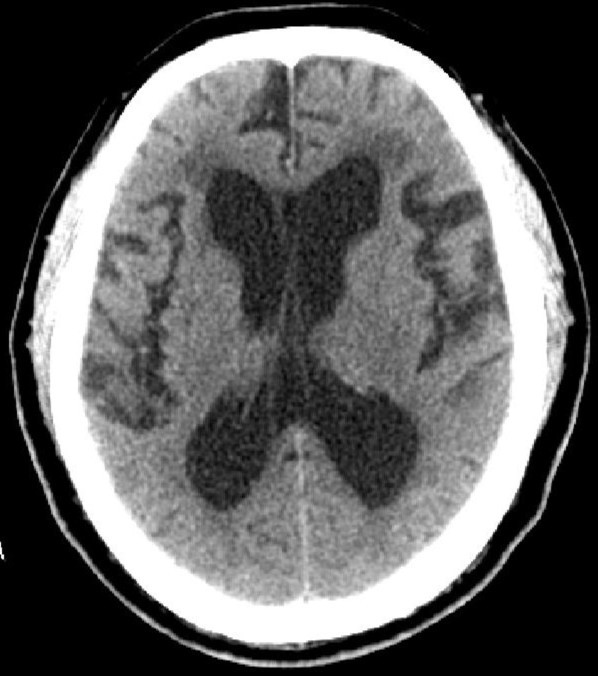

因為腦脊液的分泌、或循環(huán)、或吸收過程中出現(xiàn)障礙,則會產(chǎn)生腦積水。腦積水致腦脊液的容積增大,導(dǎo)致腦血流量及腦組織受壓并容積減少。臨床分類多樣:嬰幼兒腦積水和成人腦積水;高壓性腦積水和常壓性腦積水;腦室內(nèi)腦積水和腦外腦積水;癥狀性腦積水和無癥狀性腦積水;進行性腦積水和靜止性腦積水。比較常用的是按病因分類:交通性腦積水和阻塞性腦積水。其中交通性腦積水病因:腦脊液吸收功能障礙、蛛網(wǎng)膜顆粒發(fā)育不良、腦脊液成份改變或濃縮及腦脊液分泌過多;阻塞性腦積水病因:中腦水管狹窄或閉塞、Dandy-Walker綜合征、小腦扁桃體下疝畸形、炎癥或出血、顱內(nèi)占位性病變等。臨床癥狀:嬰幼兒有發(fā)育延遲、頭顱增大、行走障礙等;成人可有神志及精神變差、記憶力下降、頭痛頭暈、行走困難或二便失控等。頭顱CTMR可以明確診斷及辨別病因。治療主要以手術(shù)治療為主。絕大多數(shù)患者愈合良好。(神經(jīng)外科 龍青山)

正常頭顱CT          頭顱CT示腦積水